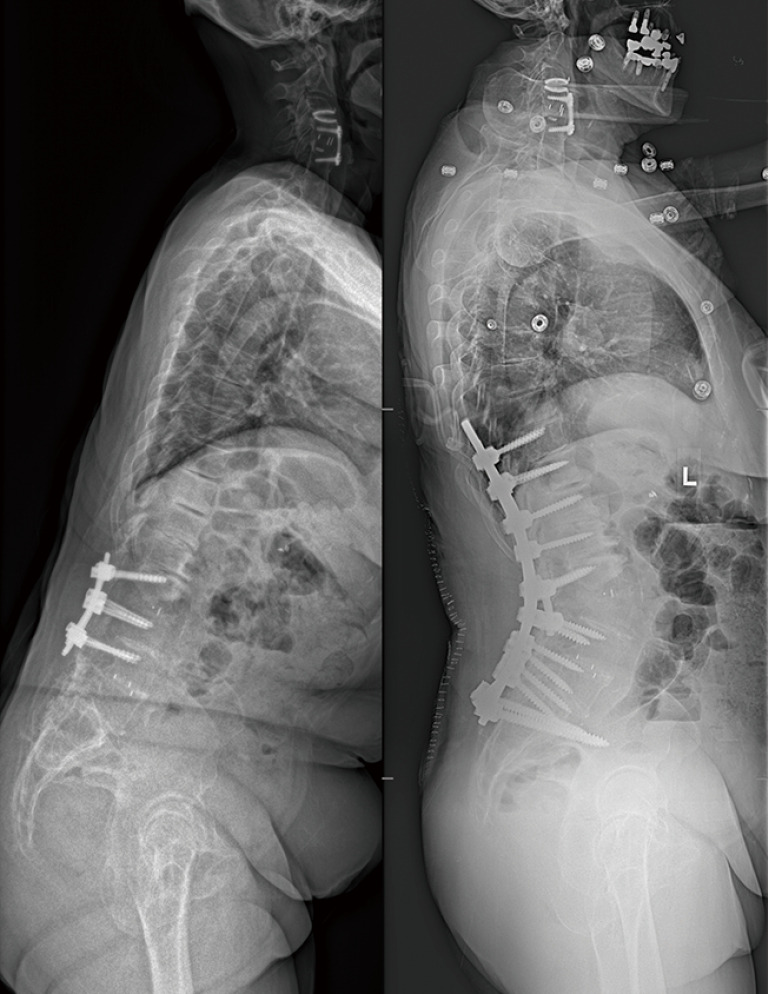

Abstract Image